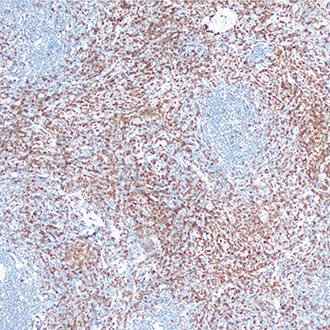

CD8

CD8 -